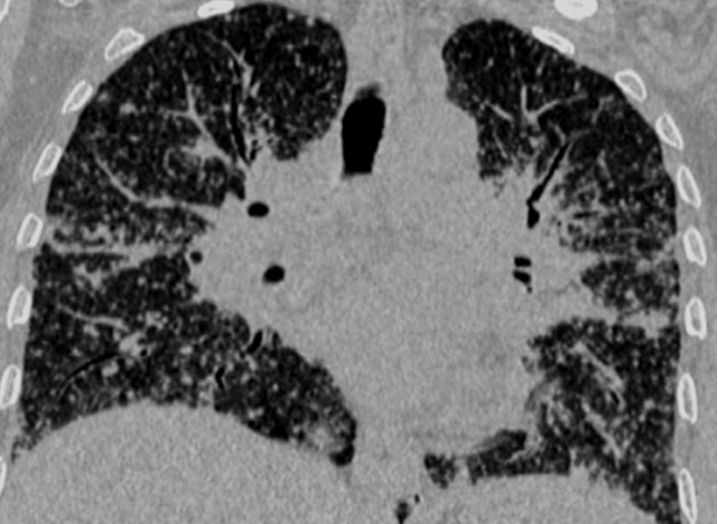

Coronal re-formatted image shows diffuse distribution of the lung nodules in both lung fields in a typical perilymphatic distribution.

A total of 32 patients had lung parenchymal lesions excluding end stage lung disease [Table/Fig-5]. The lung parenchymal findings were classified as being typical or atypical. The most common typical finding seen in 26 patients was micronodular opacities (1-3 mm in size) in a perilymphatic distribution. Perilymphatic distribution included nodules in the peribronchovascular distribution, subpleural regions and nodules along the interlobular septum. Perilymphatic distribution was most commonly appreciated in the parahilar regions and was seen as thickening and nodularity of the peribronchovascular interstitium and in the subpleural locations adjacent to the fissures [Table/Fig-6]. Areas of coalescing of the micronodules into larger nodules of varying sizes were seen in most cases [Table/Fig-7]. Atypical findings were noted in six patients. These atypical findings included patchy ground glass opacities [Table/Fig-8], focal consolidations and confluent conglomerate opacities [Table/Fig-9]. Findings of mosaic attenuation and air trapping were seen in three patients. Predominant involvement of the upper and middle zones was seen in 31 patients. In nine patients, the lesions were found involving both lungs in a diffuse manner [Table/Fig-10,11].

Perilymphatic distribution of the micronodules is the hall mark of sarcoidosis. The nodules are usually sharply defined, have a bilateral and generally symmetrical distribution and mainly involve the upper and mid zones [1,6,11]. The nodules are most frequently seen along the peribronchovascular interstitium and in the subpleural locations. Interlobular septal nodules are seen less frequently. The nodules frequently coalesce into larger nodules [3,12,13]. Lung parenchymal lesions excluding end stage disease was seen in 80% (n=32) of the patients. Presence of micronodules in a perilymphatic distribution, mainly along the peribronchovascular and subpleural distribution with frequent coalescing of nodules was the most predominant finding on HRCT in this study as seen in 65% (n=26) patients. These findings of predominantly micro nodules, their characteristic features, their typical perilymphatic pattern of distribution in the lung parenchyma, the lobar predominance, their tendency for coalescing, and their progression to end stage lung disease in a subset of patients, seen in this study are in concurrence with findings of sarcoidosis in the published literature [12,14,15].